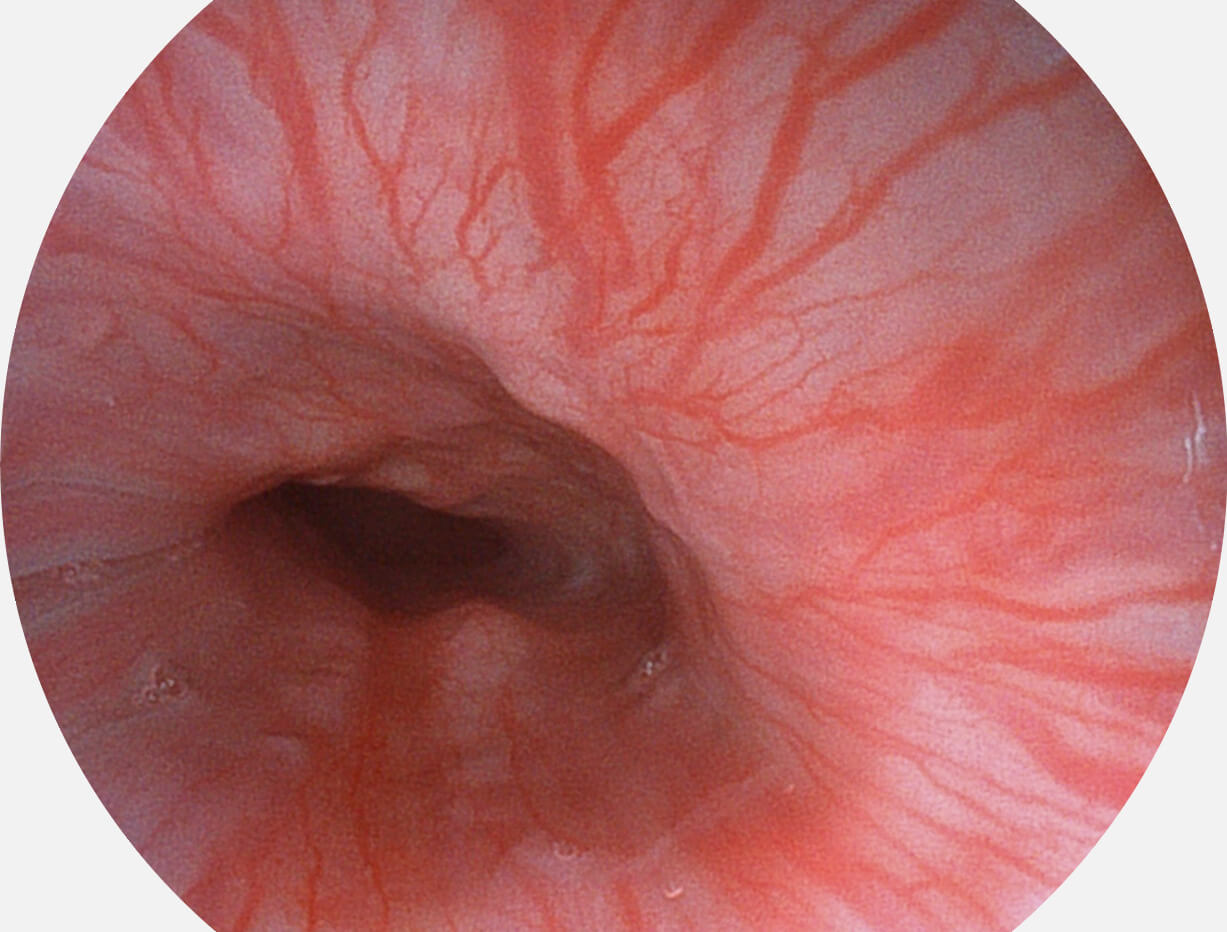

白光图像

SFI图像

采用光路合束技术,光谱自由度高,实现了更丰富的照明模式,染色模式SFI及VIST,从远景到近景,助力消化道早期疾病诊断。